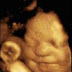

Gambar Eksklusif: Janin Tersenyum & Menangis Dalam Rahim Ibu

Foto-foto tersebut menunjukkan, bayi yang belum lahir pun ternyata mampu mengejapkan matanya, menguap, mengernyitkan dahi dan menangis.

Sampai saat ini, dokter dan orangtua percaya, janin dalam rahim ibu, tak dapat tersenyum sampai beberapa minggu setelah lahir. Tetapi ahli kandungan terkenal asal Inggris, Prof Stuart Campbell yang mempelopori teknik rekaman gambar ini, mengatakan, pendapat tersebut tidaklah benar sepenuhnya.

“Para ahli berpendapat, bayi tidak tersenyum sampai usia 6 minggu setelah lahir. Padahal, sebelum lahir pun bayi-bayi itu sering sekali tersenyum.”

Gambar-gambar ini, dibuat menggunakan ultrasound 4D, yang mencatat gema/gaung yang berasal dari rahim ibu, dan mencatatnya secara digital.

Pengamatan yang dilakukan selama berjam-jam, akan menghasilkan gambar yang membuat orangtua seperti menonton video kehidupan bayinya.